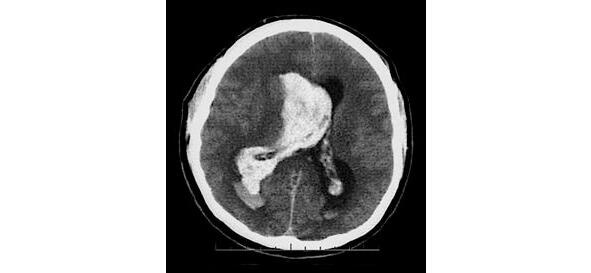

Ишемический инсульт обусловлен нарушением проходимости мозговых сосудов вследствие закупорки их атеросклеротической бляшкой, эмболом, тромбом или в результате спазма сосудов мозга различной локализации (рис. 1).

Рисунок 1. КТ-картина ОНМК по ишемическому типу в бассейне левой каротидной артерии